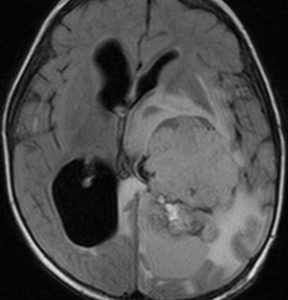

側脳室三角部に発生した大きな脈絡叢乳頭腫です。周囲に脳浮腫が高度なのですが,これでもグレード1です。大きくなると腫瘍血流が増えて,静脈鬱滞が生じて良性の乳頭腫でも腫瘍周辺脳浮腫を呈します。脳との境界が明瞭なところが脈絡叢癌との違いでもあります。